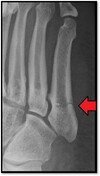

Define the following term:

Incomplete Fracture

A

Fracture through only one cortex